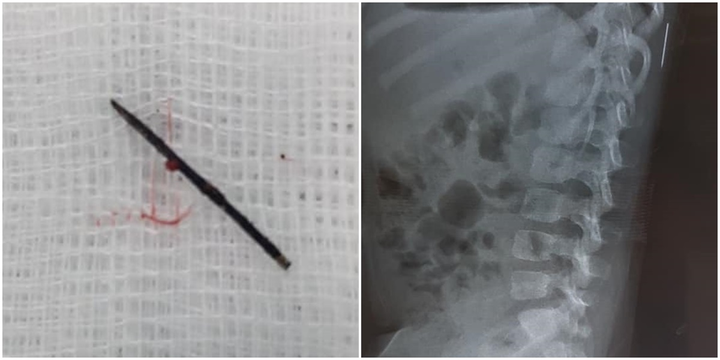

Hình ảnh dị vật là chiếc kim khâu ở phần lưng bé gái 3 tuổi ở Phú Thọ.

Ca phẫu thuật diễn ra trong một tiếng. Các bác sĩ lấy ra khỏi cơ thể bệnh nhi dị vật là 1/2 chiếc kim khâu dài 17mm đã bị gỉ đen.

Quá trình thăm khám, qua phim chụp X-quang, các bác sĩ phát hiện có dị vật trong phần mềm vùng cơ lưng trái, đốt sống 11 của bệnh nhi.